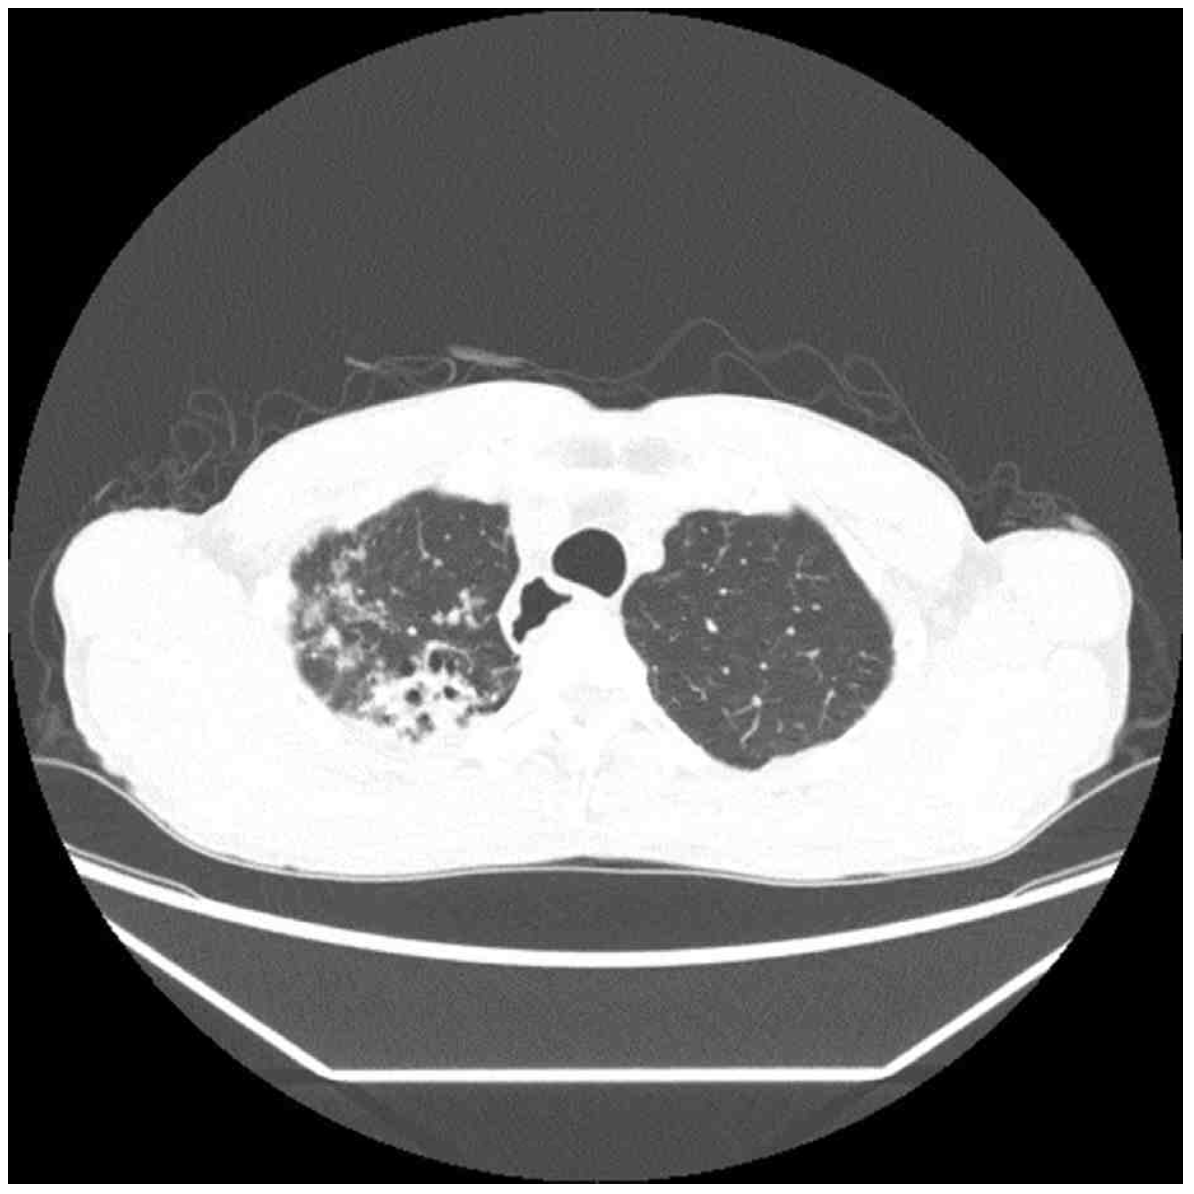

74세 남자가 6개월 전부터 기침을 한다며 병원에 왔다. 기침을 하면 가래가 조금 나오기도 하였다. 40갑•년의 흡연자 이다. 혈압 134/86 mmHg, 맥박 78회/분, 호흡 20회/분, 체온 37.1°C이다. 오른쪽 가슴에서 쌕쌕거림이 들린다. 가슴 X선사진과 가슴 컴퓨터단층촬영 사진이다. 가래검사 결과는 다음과 같다. 조치는?

CT: RULF centrilobular nodule, tree-in-bud pattern

• CXR상 RULF hazziness가 발견되며 chest CT에서도 RULF에 centrilobular nodule 및 tree-in-bud pattern이 관찰된다. 만성 기침, 가래, 미열 등의 임상 양상과 영상 소견을 종합하여 판단할 때 폐결핵을 반드시 의심해보아야 한다.